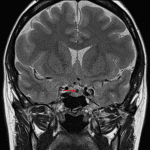

Age: 36

Sex: Female

Indication: Galactorrhea, hyperprolactinemia

- T1 hyperintense, T2 isointense rounded lesion along the superior margin of the pituitary gland measuring 9 x 8 x 6 mm

- Internal rounded area of T2 signal hypointensity measuring 3 mm in diameter

- No corresponding enhancement

- The lesion bulges into the suprasellar cistern but does not clearly contact the optic chiasm

Rathke cleft cyst